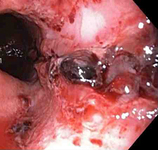

Bleeding Mallory Weiss Tear viewed on retroflexion

From the personal collection of Douglas Adler; used with permission